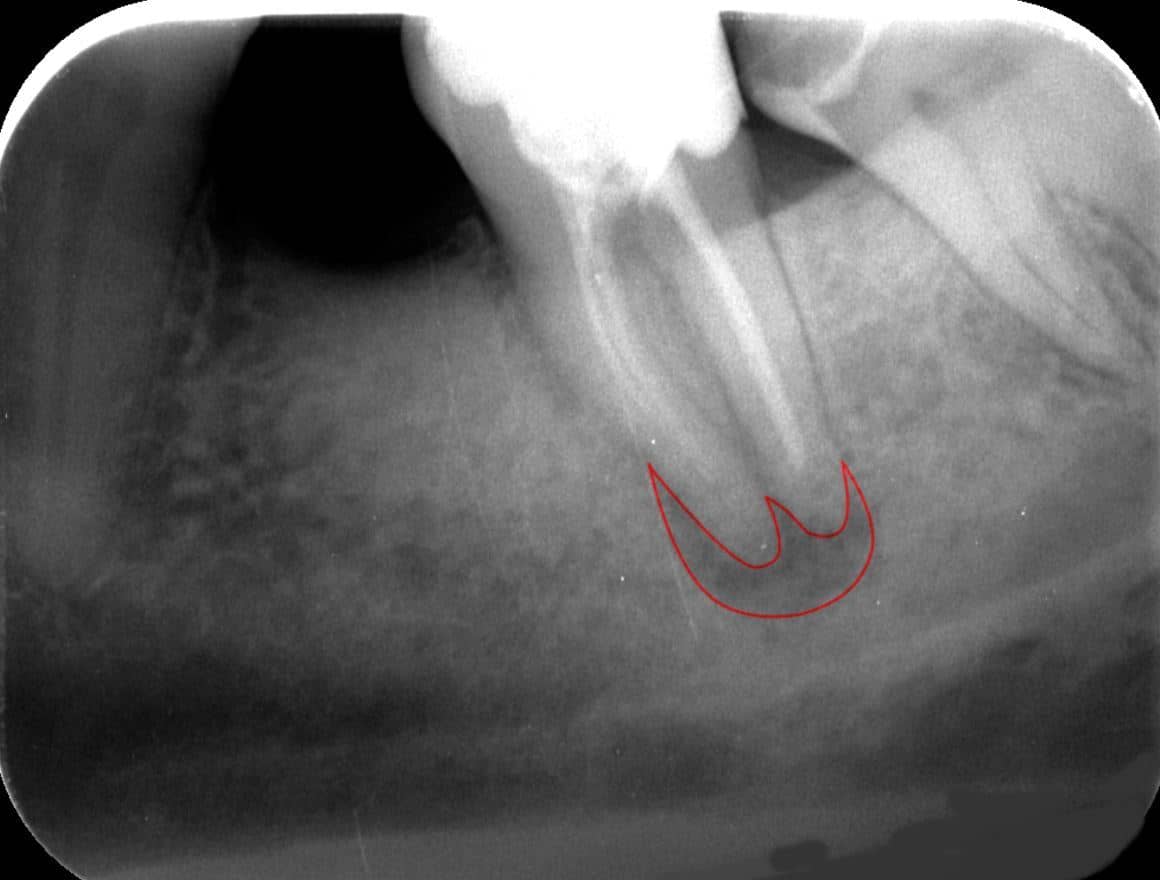

A röntgenvizsgálatok lehetnek intraorálisak és extraorálisak. Az intraorális kifejezés jelentése: szájon belüli. Ebben az esetben az érzékeny film vagy szenzor a szájon belül helyezkedik el. A sugárforrás ez esetben is a szájon kívül található. Intraorális vizsgálat pl. az úgynevezett kisröntgen. Ez az eljárás egy kisebb terület vizsgálatára alkalmas. Az alábbi képen egy foggyökérnél található gyulladás (piros vonallal kiemelve) kisröntgennel készített képét láthatjuk: